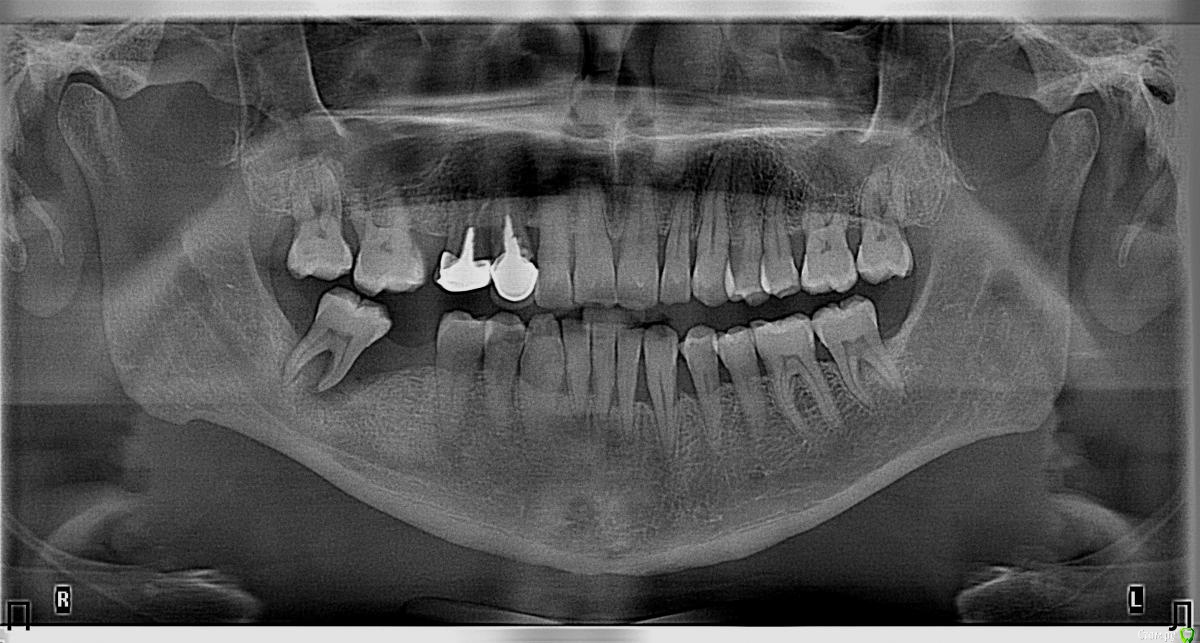

Nitrino1 Опубликовано 20 января, 2018 Поделиться Опубликовано 20 января, 2018 Коллеги помогите поставить правильный диагноз и составить план лечения, чтоб продолжительно держалосьОбъективно на всех зубах камни над и поддесневые. В 47ом зубе 3-я степень подвижность.Почистил все камни и налеты, назначил полоскание, пасту Парадонтах, удалил 47ой зуб.Сделал панорамку (до удаления) и фотки тоже до удаления.Должен составить план лечения... Ссылка на комментарий

red_butler Опубликовано 21 января, 2018 Поделиться Опубликовано 21 января, 2018 Хронический генерализованный пародонтит тяжелой степени, в ремиссии (по МКБ-10 Хронический генерализованный пародонтит, код К0531) Ссылка на комментарий

Nitrino1 Опубликовано 21 января, 2018 Автор Поделиться Опубликовано 21 января, 2018 Хронический генерализованный пародонтит тяжелой степени, в ремиссии (по МКБ-10 Хронический генерализованный пародонтит, код К0531)какой план лечения вы бы порекомендовали? интересует момент с нижними резцами, их шинировать или же удалить? на верхних 6ках тоже ситуация не очень. Вообще какую тактику выбрали бы?И еще просьба, посоветуйте что можно почитать современное на тему парадонтитов и парадонтозов, то что у меня есть это старое уже Ссылка на комментарий

almaz7888 Опубликовано 3 февраля, 2018 Поделиться Опубликовано 3 февраля, 2018 Шинирование нижних резцов в связке с соседними зубами после предварительно го депульпирования зубов. В последующем лоскутная операция. Избирательное пришлифовывание. 1 3 Ссылка на комментарий

molchanoff Опубликовано 4 февраля, 2018 Поделиться Опубликовано 4 февраля, 2018 Удалить подвижное. Кюретаж того что останется. Два съемника и убедившись в стабилизации процесса имплантация. Ссылка на комментарий